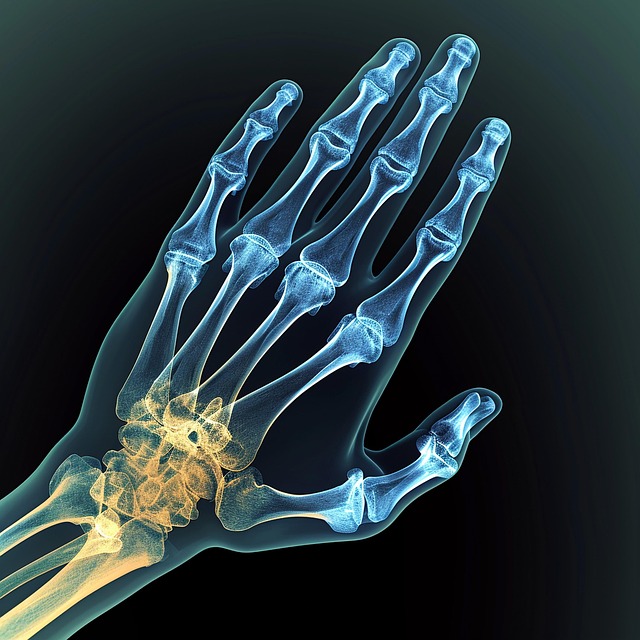

손목 터널 증후군 증상, 원인 및 치료법

빠르게 변화하는 오늘날의 디지털 사회에서 손목터널증후군(CTS)은 많은 사람에게 흔한 문제입니다. 전문 타이피스트, 게이머, 스마트폰 사용 시간이 많은 사람이라면 손목터널증후군에 걸릴 위험이 그 어느 때보다 높습니다. 이 글에서는 손목 터널 증후군의 증상과 원인, 다양한 치료법을 살펴보며 복잡한 손목 터널 증후군에 대해 자세히 설명합니다. 질환을 이해하면 예방을 위한 사전 조처를 하거나 증상이 나타나면 적절한 치료를 받을 수 있습니다.  손목 터널 증후군(carpal tunnel syndrome)손목 터널 증후군은 팔뚝에서 손바닥으로 이어지는 손목의 중앙 신경이 손목에서 압박받을 때 발생하는 질환입니다. 이 신경은 엄지손가락과 손가락(새끼손가락 제외)의 손바닥 감각과 손가락과 엄지를 움직이는 손의 작은 ..